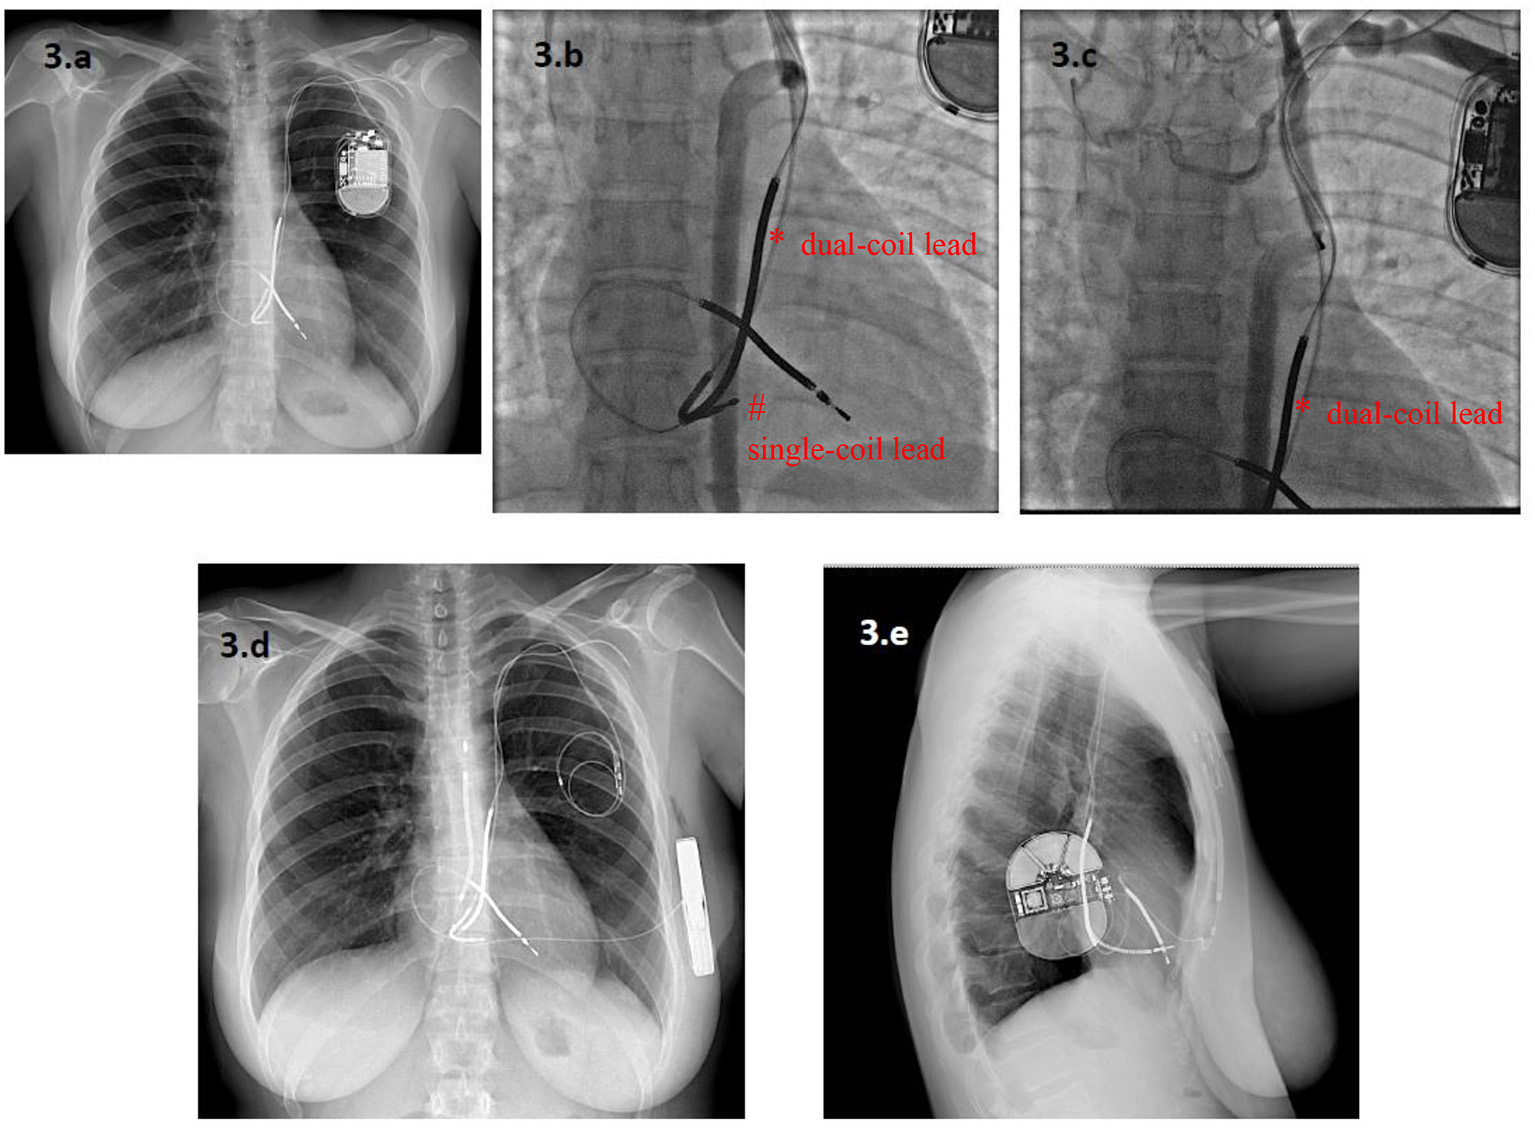

According to the data from the ELECTRa study (19), lead malfunction is becoming a more frequent indication for lead extraction than it was in the past (30). Currently, a class IIa recommendation exists for either lead abandonment or removal, followed by T-ICD reimplantation (4). Extraction avoids the potential long-term risks of abandoned leads and allows magnetic resonance imaging to be performed. Indeed, although growing aggregate of data seems to question this (31), the presence of abandoned leads remains an absolute contraindication for magnetic resonance imaging. Nonetheless, in this series, the strategy of lead abandonment and S-ICD implantation avoided the possible complications associated with the extraction procedure, and appeared to be feasible and safe, with no significant increase in adverse outcomes in patients not requiring pacing. In current clinical practice (15), an S-ICD is preferred in younger patients and in those with a life expectancy longer than 10 years, who will probably survive their ICD leads (10). This may also apply to patients who experience ICD lead malfunction. Indeed, lead malfunction occurs most frequently in younger patients, both because they are more active and because a longer lead-dwelling time results in more prolonged lead stress (32). If the use of the S-ICD therefore appears justified in the event of lead malfunction, when pacing is not required, the actual need to extract malfunctioning leads may remain an open question, also in the light of the positive outcomes reported with the use of S-ICD after transvenous ICD extraction (17). In clinical practice, the risk profile of the patient, the number of leads, the time from the first implant are variables that may guide the management, as well as performing venography and discussing with patient before making a decision (Figure 3).

Figure 3

A 33-year-old woman with a Long QT Syndrome received a single-chamber T-ICD and a dual-coil lead via a persistent left superior vena cava (PLSVC) after a cardiac arrest. A new single-coil ICD lead was added five years later owing to malfunction of the first one, which was abandoned (a). After seven years, the second ICD lead also malfunctioned. Angiography showed complete occlusion of the PLSVC, with a variant venous circulation from an accessory hemiazygos vein. The dual-coil ICD lead (*) and the single-coil lead (#) are visible in (b,c). In this setting, lead extraction was considered to be at very high risk of venous laceration, while implantation of a new lead from the right side was deemed inappropriate because of the patient's young age. Finally, an S-ICD was implanted and both leads were abandoned (d,e). * dual-coil lead # single-coil lead.